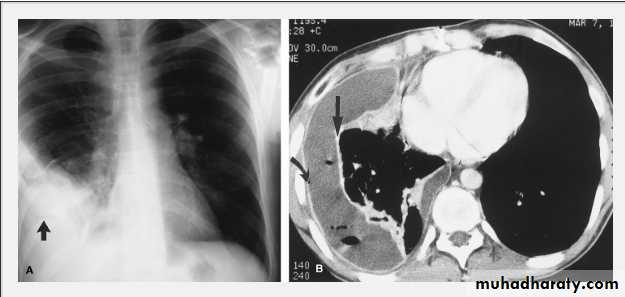

Massive pleural effusion with mediastinal shift to the left.

(A) Chest radiograph

(B) CT coronal reconstruction. A massive effusion displaces the mediastinum to the left. CT shows the important pleural effusion together with the enhanced atelectatic left lung.

Note also the depression of the right hemidiaphragm (arrows).